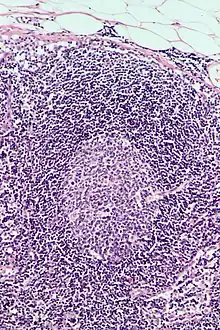

This is a list of Immune cells, also known as white blood cells, white cells, leukocytes, or leucocytes. They are cells involved in protecting the body against both infectious disease and foreign invaders.[1]

| Image | Name | Subtype | Class | Alternate Names | Diametere (μm) | Main targets | References |